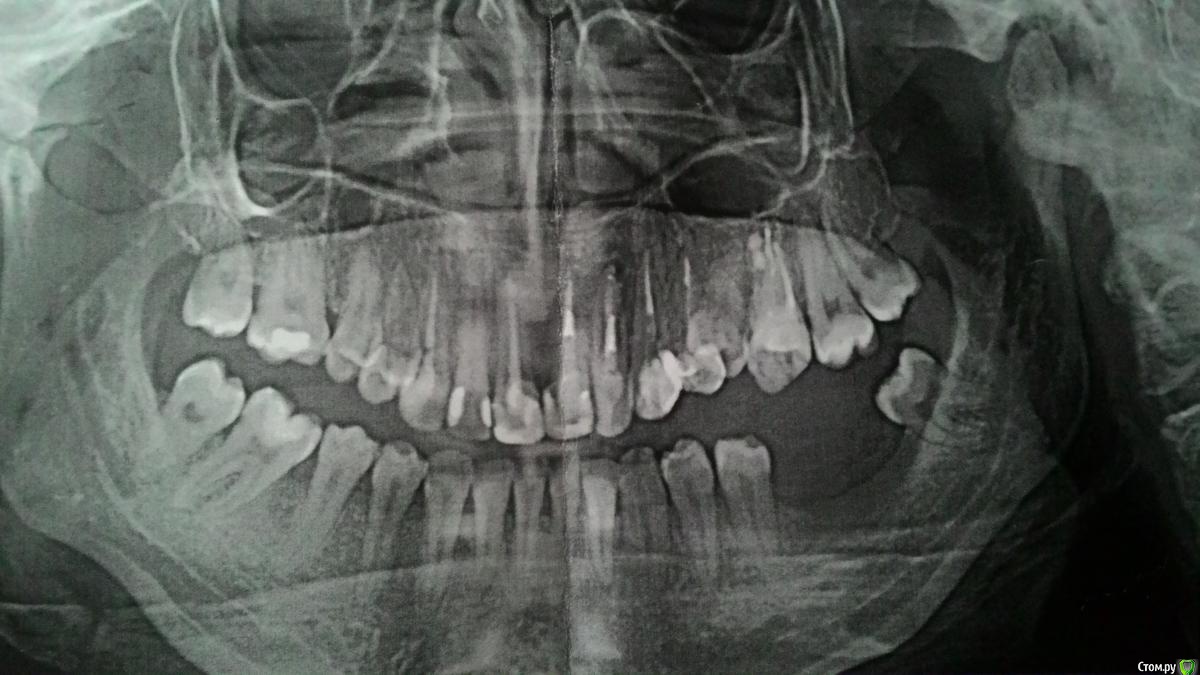

Самойлова Опубликовано 25 октября, 2016 Автор Поделиться Опубликовано 25 октября, 2016 Добрый день! Мне 25 лет. Снимок ЗД показал, что у меня головка мыщелкового отростка атрофировалась. По словам врача хирурга, это врожденная патология. Лицо, слава Богу, не изменилось, чуть, почти незаметно смещен подбородок. Прикус глубокий, боковые зубы смыкаются. В детстве удалили два нижних зуба ( 6 и 7-й) год назад рядом с пустующим местом прорезался зуб мудрости. Сейчас большая атрофия кости, на нижних зубах рецессия десен и клиновидные дефекты. На нижней челюсти нужна, как сказали, вестибулопластика. Врачи сказали, что имплантация возможна только после костной пластики. Многие зубы лечены, поэтому, боясь потерять зубы, отказалась от ортодонтии. Добавляю панорамный снимок Ссылка на комментарий

Kazankov.Egor Опубликовано 30 октября, 2016 Поделиться Опубликовано 30 октября, 2016 Мыщелковый отросток может атрофироваться вследствие длительной компрессии сустава (глубокий прикус), снимок с улыбкой))) Это с большой долей вероятности может означать просто наклон рентгеновской трубки. Лучше выложить объемный снимок. Ссылка на комментарий